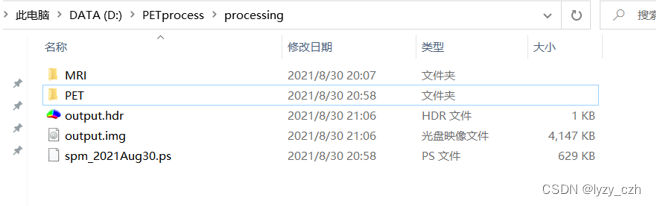

转换完成后输出如下:

这里生成了多个hdr/img的图像,只需要选择其中最好的一个即可(我看起来都是一样的)

此时在输出目录下生成如下文件:

生成如下文件:

生成如下文件:

打开output图像如下: